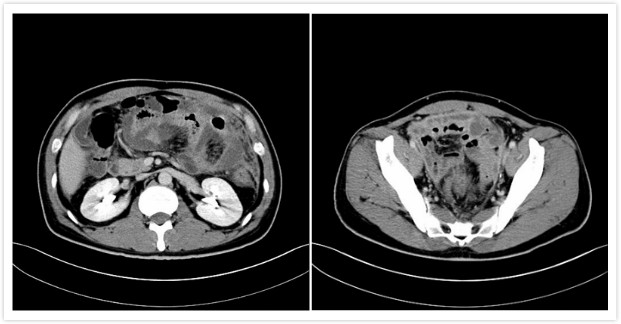

患者术前病例CT图片

由于疾病的影响,身高183厘米的吴先生,体重也从原先的197斤降低到手术前的140斤左右,且由于疾病反复发作,工作受阻收入减少,加上这些年累计就医花费大约有百万之多,对于吴先生这样的普通家庭来说经济负担非常大。